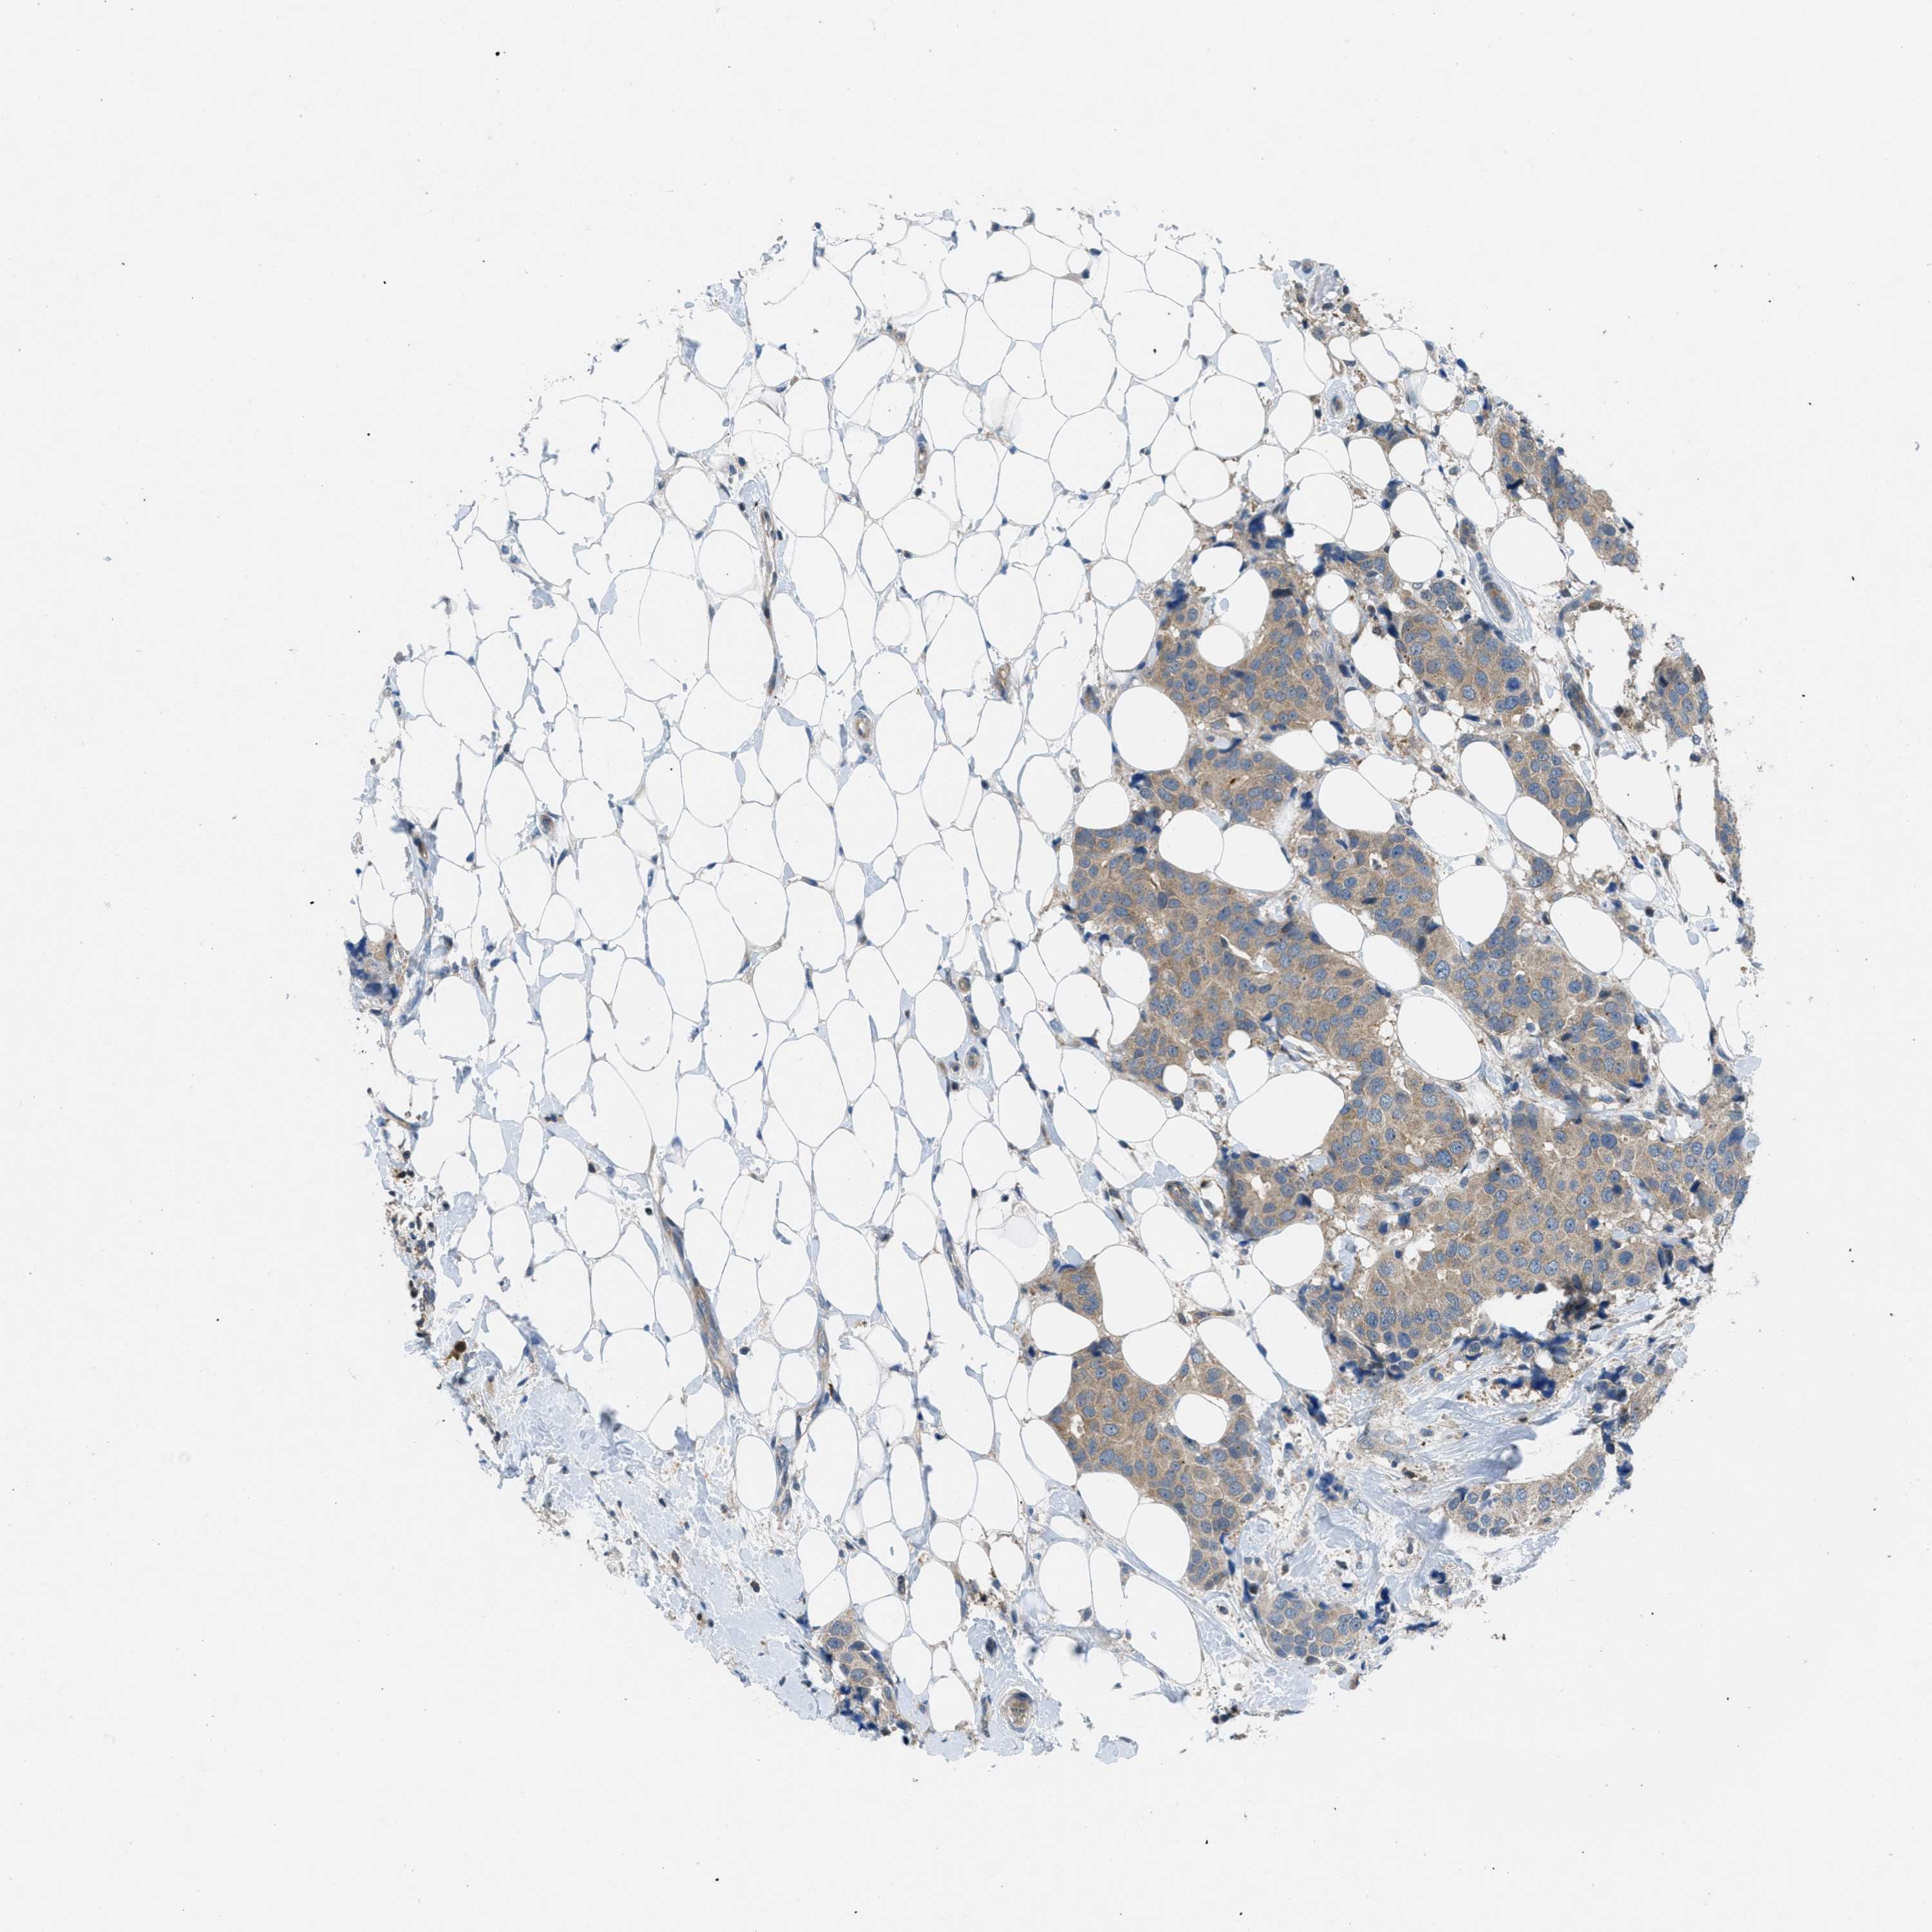

CANCER BREAST CANCER Show tissue menu

BRCA TCGA BRCA VALIDATION PROTEIN EXPRESSION